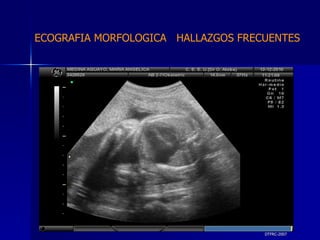

DTFRC-2007 ECOGRAFIA MORFOLOGICA  HALLAZGOS FRECUENTES   MATERIAL Y METODO ES UN ESTUDIO DESCRIPTIVO, RETROSPECTIVO  DE ESTUDIO ECOGRA FICOS REALIZADOS ENTRE MARZO 07 A MARZO 08 EQUIPO DE ALTA RESOLUCION   VOLUSON 730 PRO  MEDISON SA 8000 live MEDISON SA 8000SE CRITERIO DE INCLUSION:   POBLACION GENERAL    GESTACIONES  20 a 24 SEMANAS   UNIVERSO  N 211

DTFRC-2007 ECOGRAFIA MORFOLOGICA  HALLAZGOS FRECUENTES   Sistema Nervioso Central  8  Cardiovascular  0 Genitourinario  6 Musculos Esqueleticos  2 Gastrointestinales  2  Otros  12  Total  30   NUMEROS DE ANOMALIAS POR SISTEMA n N  211

DTFRC-2007 ECOGRAFIA MORFOLOGICA  HALLAZGOS FRECUENTES   SISTEMA NERVIOSO CENTRAL TOTAL  8  26 % 1 HIDROCEFALIA 2 VENTRICULO MEGALIA 4 QUISTE DE PLEXO COROIDEO 1 ANENCEFALIA